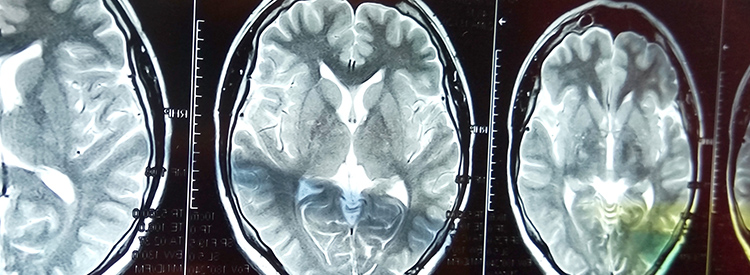

中風治療進展緩慢。如果在最初幾分鐘內進行治療,可以在急診室或醫院使用特殊藥物(阿替普酶或組織纖溶酶原激活劑)來逆轉或限制缺血性中風造成的損害。這種藥物可以分解阻塞血管的凝塊。如果在最初的幾分鐘到幾小時內使用,可以避免或限制對大腦的任何損害。在使用阿替普酶之前,必須進行 CT 成像來確定中風類型,以確認中風不是出血性的。由于阿替普酶會分解血栓,因此如果用于出血性中風,可能會導致嚴重惡化或死亡。有時會治療出血性中風以避免進一步出血。